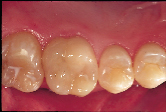

| Figure 3a: A reattachment procedure for the fractured central incisors was done as an interim treatment option. | Figure 3b: Definitive treatment can be delayed until tooth and gingival maturation is complete. |

The corollary to acknowledging the probationary nature of our restorative efforts is that definitive treatment can justifiably be deferred until tooth and gingival

maturation is complete. The fractured central incisors depicted in Figs. 3a and 3b are representative of this principle. The pulps of both teeth were exposed following a traumatic episode. Following pulp capping using the total etch technique, the fractured incisal tooth fragments were reattached by means of a dentin bonding agent.6 Two and a half years later both teeth are vital, but the reattached fragments are discoloured and the patient is dissatisfied with the visible tooth fragment (Fig. 3a). The reattachment procedure was delivered as an interim treatment that not only maintained the biological seal of the pulpal tissues but also allowed for subsequent preparation of veneers (Fig. 3b).